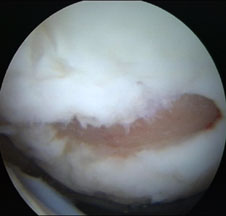

Chirurgul trebuie sa fie foarte atent atunci cand examineaza posteriorul condililor femurali. Daca se semnaleaza orice vatamare/rana/deteriorare pe suprafetele articulare, trebuie sa se cerceteze atent calitatea cartilajului. Orice flapsuri instabile sunt inlaturate prin folosirea unui aparat de ras electric artroscopic sau curette. Apoi, un curette este folosit pentru a debrida stratul de cartilagiu calcifiat de la baza in toata grosimea defectului. Acest pas se bazeaza pe activitatea lui Frisbi, care a demonstrat vindecarea suprafetei articulare superioare la un cal, cand stratul cartilagiului calcifiat este indepartat. Cand indepartam stratul cartilajului calcifiat, in general nu se foloseste un aparat de ras. Cu un aparat de ras este dificil de controlat cantitatea de os eliminat, si este posibil ca osul subcondral sa fie afectat.

Dupa indepartarea cu succes a stratului de cartilaj calcifiat, o andrea este folosita pentru a face mai multe gauri mici (mirofracturi) in osul expus al defectului condral aflate la distanta de 1-2 mm. Trebuie lasata o punte de oase potrivita intre gauri. Tehnica de microfracturi are numeroase avantaje fata de foraj. Mai intai de toate, creaza o leziune termala mai mica. Mai mult, cu microfracturi chirurgul este capabil sa intre in zonele dificile ale suprafetei articulare cu un control mai bun asupra adancimii de patrundere. La finalizarea microfracturii, o suprafata aspra este generata pentru aderenta cheagului de sange care contine celule mezenchimale nediferentiate de la osul subcondral. Trebuie avut grija ca cele mai marginase parti ale leziuni sa fie patrunse de andrea pentru a ajuta la vindecarea tesutului reparator la imprejmuirea suprafetei articulare. Odata ce microfractura este finalizata, pompa artroscopica este oprita pentru a se asigura ca sangerarea maduvei curge din gaurile mici umpland defectul.[54]